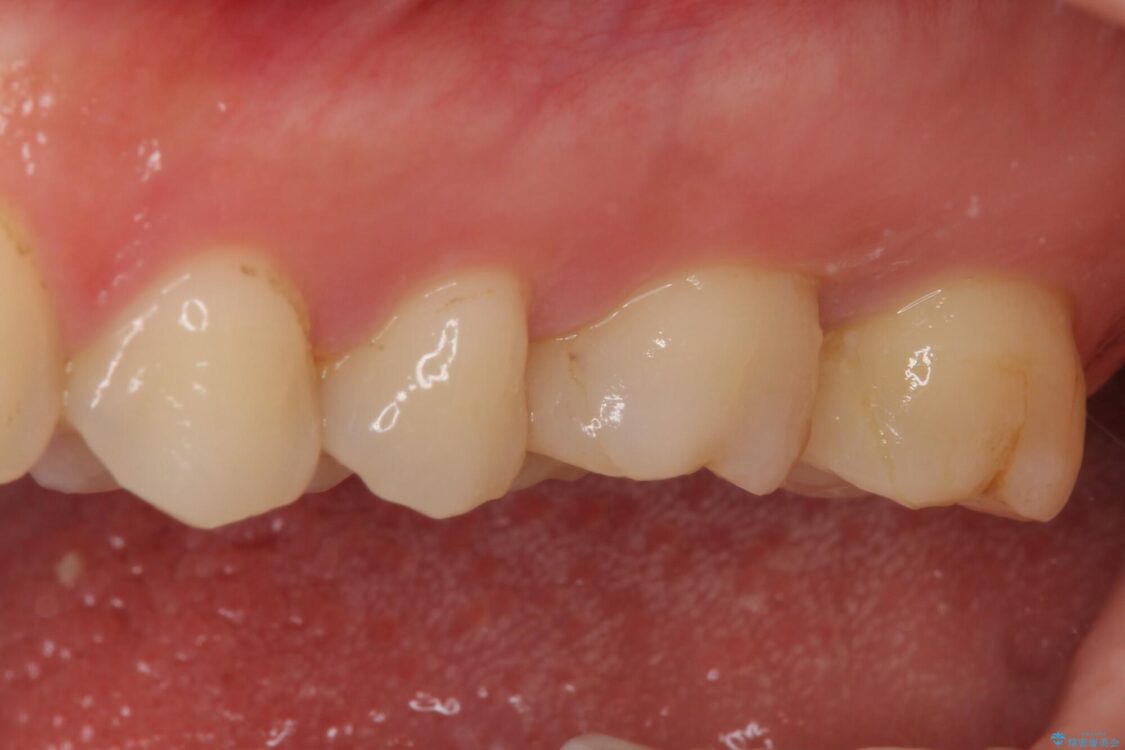

奥歯がズキズキと痛み、食事で噛むことができないとのことで来院された患者様です。 以前治療を受けたとき、むし歯が大きかったため、神経組織が炎症を起こす可能性があると指摘をされていたとのことでした。

治療前

• 奥歯がズキズキと痛む 奥歯の虫歯治療 治療前画像